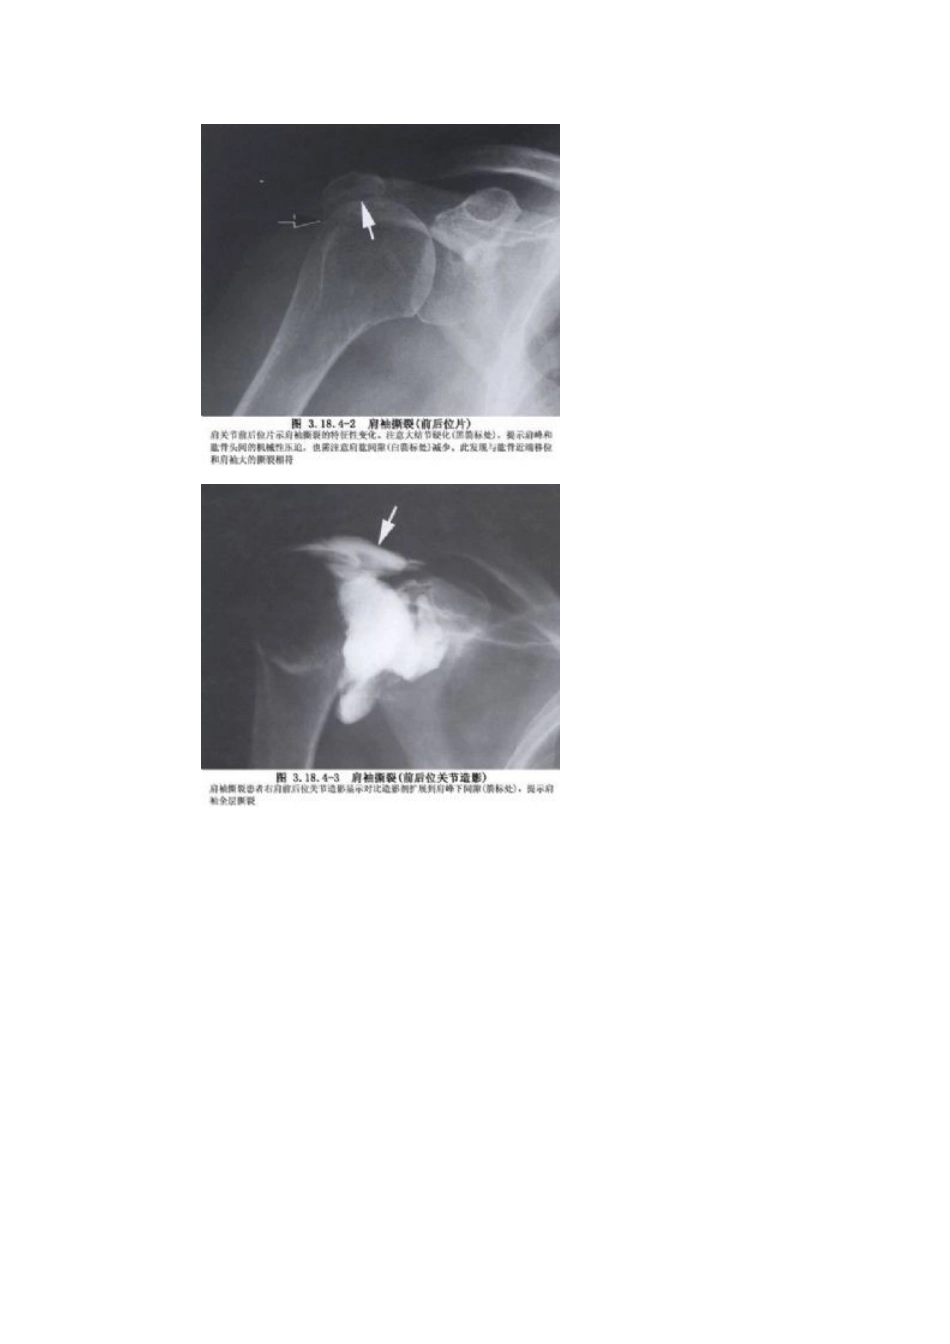

肩关节镜手术1 拼音jiān guān jíe jìng shǒu shù2 英文参考operarion of the shoulder joint by arthrocopy3 手术名称肩关节镜手术4 分类骨科/关节镜外科手术5 ICD 编码80、21016 概述肩袖就是由冈上肌、冈下肌、肩胛下肌与小圆肌组成,起于肩胛骨。冈上肌从肩胛骨得上面,冈下肌、小圆肌从其后面,肩胛下肌从前面围拥肩胛骨,附着在肱骨解剖颈得上半。冈上肌止于肱骨头大结节得上压迹、冈下肌止于中压迹、小圆肌止于下压迹,肩胛下肌止于肱骨头小结节,在肱骨头解剖颈处形成袖套状结构。对于盂肱关节有支持与稳定 作用 (图3、18、41)。肩袖损伤在中老年与肩关节 创伤 中比较常见,其发病率占肩关节疾患得17%~41%,1834 年 Smith 首先名为“肩袖撕裂”(图 3、18、42~3、18、46)。一般将肩袖损伤分为三期:第 1 期肩袖出血 水肿 。当肩关节外展上举时,肩袖受到肩峰与喙肩弓反复得、微小得撞击与拉伸,肩峰前下方骨赘形成,使肩袖撞击发生 充血 水肿、变性乃至冈上肌腱断裂。亦有讨论发现肩袖撕裂随年龄得增长而增多,而肩峰下骨性改变则与年龄无关,从而认为撞击综合征并不就是引起肩袖损伤得主要原因,而就是肩袖退变与外伤共同作用得结果。肩袖损伤得非手术治疗方法包括:休息、给予 NSAIDs 消炎镇痛药物、物理疗法、局部封闭与各种有利于肌肉力量及功能恢复与练习得综合 康复 方法。对保守治疗无效者采纳开放手术肩袖缝合术修复。关节镜下修复肩袖具有创伤小,不破坏三角肌,有利于功能康复等优点。7 适应症肩关节镜检查就是一种诊断方法,因此并无绝对指征非用关节镜不可。但一些肩部疾病应用关节镜检查后可以进一步明确诊断与更清楚地了解疾病得病理改变,有时还可进行手术处理。下列情况可考虑进行关节镜手术。1、关节游离体 明确诊断、摘除游离体。2、痛性关节不稳定(习惯性脱位或半脱位) 明确关节囊、盂唇损伤部位,可行修补手术。3、肱二头肌断裂 了解断裂得程度,切除断端,减轻痛苦。4、肩袖断裂 急性完全性肩袖损伤,由于漏液关节囊不能膨起,不宜行关节镜检查。对慢性肩袖断裂可明确病变情况,对不完全损伤可修整断端减轻痛苦。5、骨关节炎 清创,冲洗。6、肩化脓性关节炎 清理冲洗。7、肩峰撞击综合征 行肩峰下关节镜检查,亦可行肩峰切除术。8 禁忌症1、肩部软组织有化脓性炎症者。2、有全身麻醉禁忌证者。9 术前准备1、术前应进行详细体征及 X 线等检查,大致明确病变得部位,以便术中重点观察。2、术前...